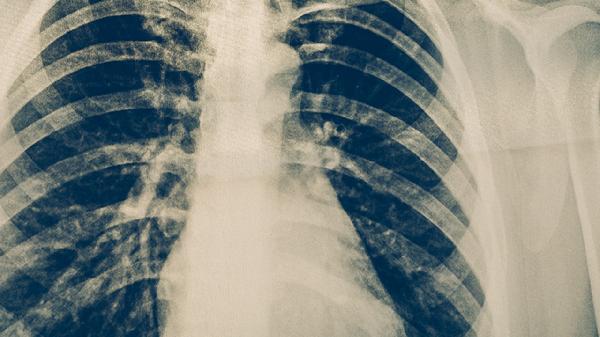

肺结核通过中医治疗可以缓解症状,但无法完全替代西医抗结核治疗。肺结核的治疗需以西医抗结核药物为主,中医可作为辅助手段改善体质、减轻药物副作用。主要有中西医结合治疗、中药调理、针灸辅助、饮食调养、情志调节等方式。

规范的四联抗结核药物(异烟肼片、利福平胶囊、吡嗪酰胺片、乙胺丁醇片)是根治肺结核的核心方案。中医可在医生指导下配合使用百部止咳糖浆、百合固金口服液等中成药,帮助缓解咳嗽、盗汗等症状。治疗期间需定期复查胸部CT和痰培养。

肺结核患者需严格完成6-8个月的抗结核疗程,中医治疗期间不可自行停用西药。注意保持居室通风,佩戴口罩防止飞沫传播,餐具应煮沸消毒。每月复查肝功能,出现视力模糊、皮肤黄染等药物不良反应时及时就医。恢复期可适当进行太极拳等温和运动增强肺功能。